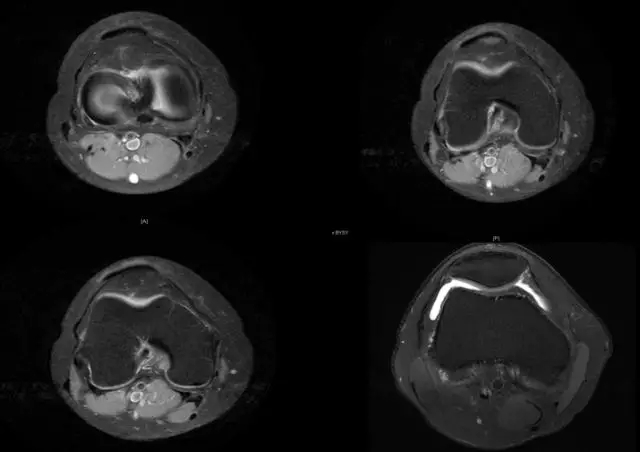

磁共振扫描在关节运动损伤诊断中的应用

关节扭伤常常导致膝关节相关韧带结构的损伤,如何及时发现这些损伤并进行相关的治疗,是我们临床医师常常面临的问题,除了相关病史、临床体征之外,磁共振扫描也是重要的诊断依据

韧带结构:形态,张力,质地,连续性

半月板:完整性,形态,质地

segond骨折

外髁骨擦伤(Kissing -sign)

陈旧性前交叉韧带断裂